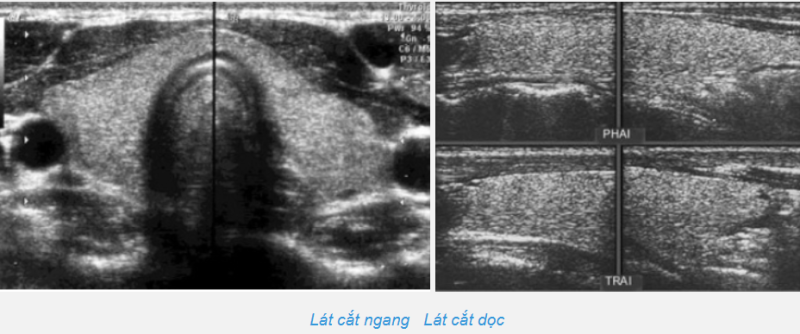

Với đầu dò 2D và hai đường cắt dọc và ngang, mỗi thùy giáp đo được 3 thông số: D: chiều dài thùy (cm); R: chiều rộng thùy (cm); và S: chiều sâu / bề dày thùy (cm)

Dùng công thức Gutekunst để tính thể tích thùy tuyến giáp như sau:

V = 0,479×D×R×S; Thể tích toàn bộ tuyến giáp: V thùy trái + V thùy phải

Thể tích trung bình của người lớn Việt Nam là 18 +/- 6 cm3.